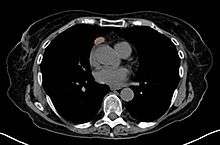

When a thymoma is suspected, a CT/CAT scan is generally performed to estimate the size and extent of the tumor, and the lesion is sampled with a CT-guided needle biopsy. Increased vascular enhancement on CT scans can be indicative of malignancy, as can be pleural deposits.[1] Limited biopsies are associated with a very small risk of pneumomediastinum or mediastinitis and an even-lower risk of damaging the heart or large blood vessels. Sometimes thymoma metastasize for instance to the abdomen.[3]

The diagnosis is made via histologic examination by a pathologist, after obtaining a tissue sample of the mass. Final tumor classification and staging is accomplished pathologically after formal surgical removal of the thymic tumor